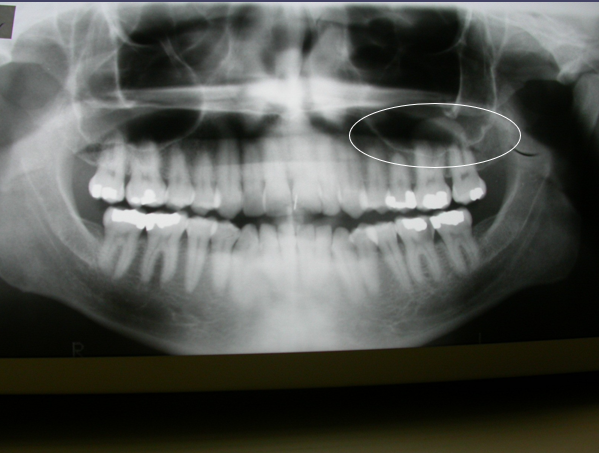

( in term of Radiology)

Appears as a dome shaped elevation of the floor of the sinus

Antral Pseudocyst

Antral Pseduocyst are NOT Mucoceles

Mucoceles would have more of meniscus-like

appearancewhere it would come up tothe edge of

the sinus

Aneurysmal Bone Cyst

✎ A dome shape swelling on the floor of the sinus that’s associated with some _sort of inflammation of tooth of t_he premolar caused inflammation underneath the apex of the bone (right) and then that leads to accumulation of fluid which causes the sinus lining to elevate off the bone and fill with fluid

✎ After root canal therapy and once the infection gets under control, these will typically resolve on their own